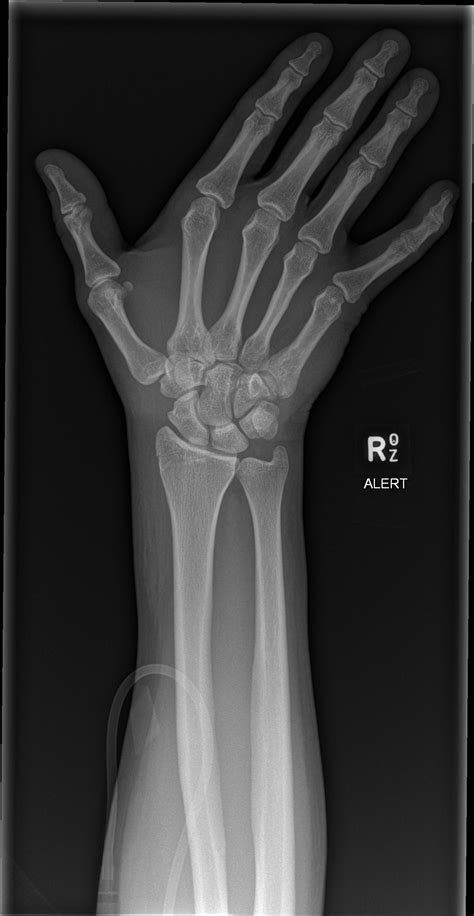

Diagnosing a fractured triquetral bone involves a combination of physical examination and imaging tests. The diagnostic process typically includes:

• Physical examination: A healthcare provider will assess the wrist for swelling, tenderness, and range of motion.

• X-rays: Standard X-rays can often reveal a fracture in the triquetral bone. However, due to the small size of the bone, additional views or specialized imaging may be required.

• CT scan: A computed tomography (CT) scan provides detailed images of the bone and can help identify fractures that are not visible on standard X-rays.

• MRI: Magnetic resonance imaging (MRI) can be used to assess soft tissue injuries and provide a more comprehensive view of the wrist joint.

In some cases, a combination of these imaging tests may be necessary to confirm the diagnosis and determine the extent of the injury.